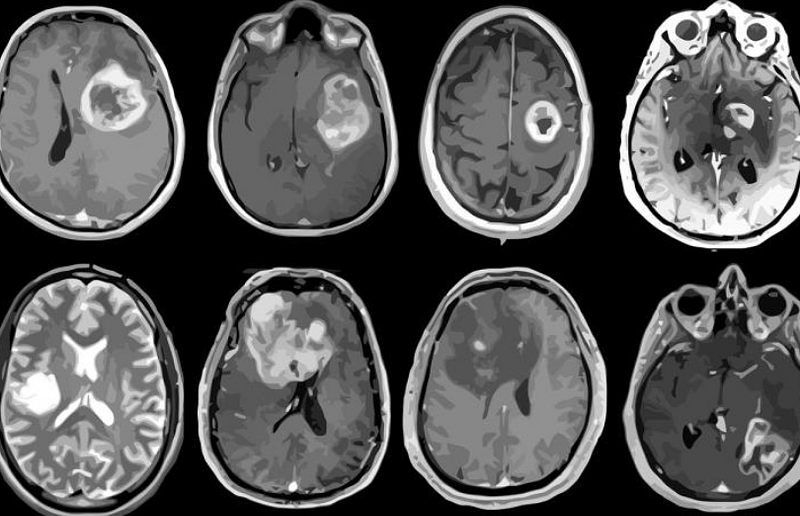

Background: Glioblastoma is a brain cancer that is very aggressive in nature and known for its short median survival time (between 12 and 14 months).  We focused on looking at the different imaging modalities (T1, T1Gd, T2, and FLAIR) because each give a different look at the tumor. For instance, T1 with gadolinium visualizes the bulk of the tumor and T2 shows edema and immune response from invading tumor cells. Putting together these four images from one single brain scan can present the big picture and provide more information than one single scan on its own.

Data and Image Processing: We included 52 cases in this analysis, 32 males and 20 females. All images were from pretreatment and each case had to have had at least 2 MRI sequences listed above on the same date.  For the data standardization process, there was registration, brain masking, CSF masking, normalization, tumor vs. normal labeling, then feature extraction. The features taken from each voxel were mean, standard deviation, skew, kurtosis, and range.

Intensity Feature Correlations: Mean intensities and image correlations for each imaging pair from each patient case and each image feature were calculated for the whole brain. Correlation between the mean T2 and FLAIR intensities show different in the tumor region of the brain.

Predictability from Imaging Features: We trained both a logistic regression and forest models from normal brain and tumor regions using all features. The best model included T1Gd and T2 features using random forest. In addition, it was found that mean T2 intensity was the most important predictor.